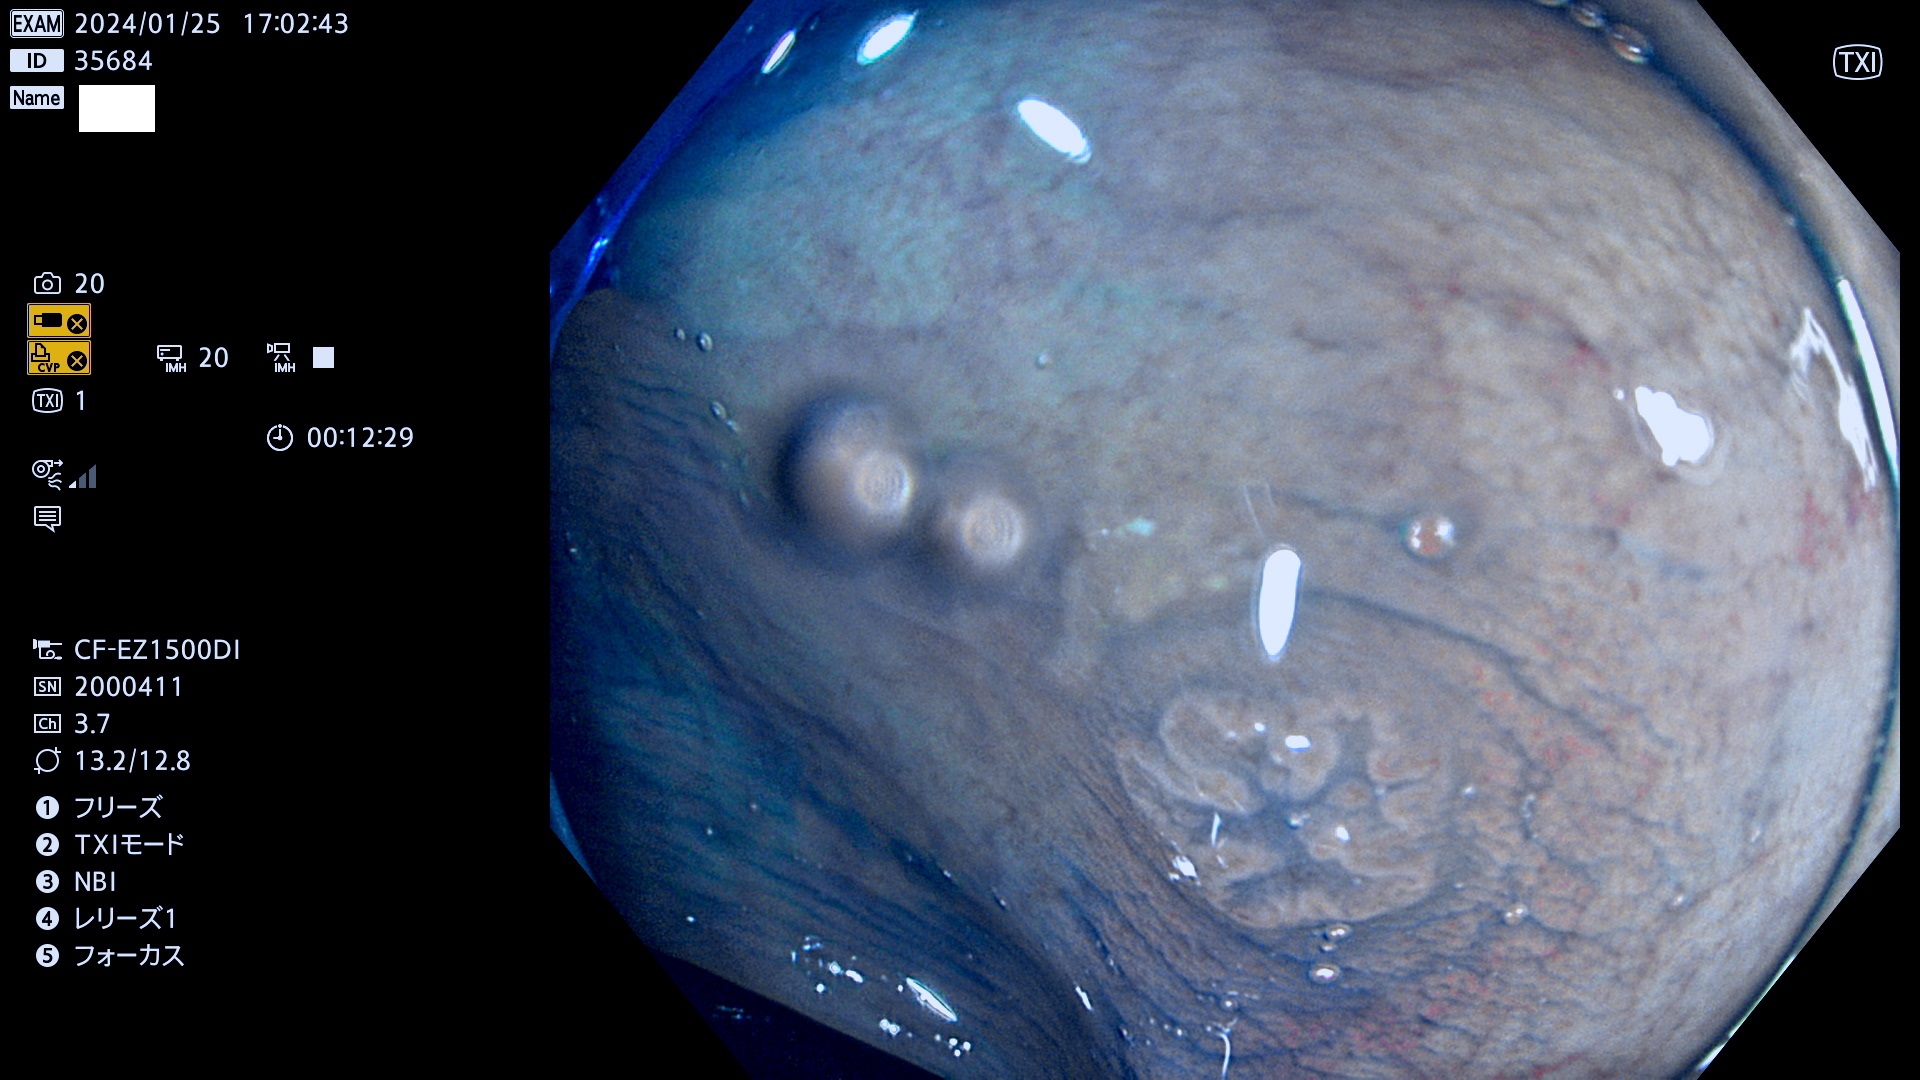

表面型腺腫(Flat Adenoma)の中で、完全に平坦な物をUb、陥凹している物をUcと呼びます。平坦隆起型(Ua)よりも、発見が難しく危険な病変です。

専門的)何故、陥凹していると危険? 癌遺伝子の変異が蓄積すると細胞分裂が盛んになり隆起するのでは?と通常は思われるでしょう。しかし実際は逆です。これは2022年の記事にある「細胞はストレスに直面したら細胞分裂を止める(細胞老化に入り休眠する)という生命の基本的現象」によるものです(Oncogene Stress)。細胞老化を起こすのが癌抑制遺伝子で、この安全装置(ブレーキ)が壊れると癌になります(休眠からの覚醒)。ですから陥凹は「まだ癌では無いが癌化の直前」を意味します。特に「小サイズなのに陥凹している」病変は短期間に腫瘍進化(⇒2021年記事)が起きたことを意味します(=ゲノム不安定性

専門的)Uc=De Novo癌? 内視鏡の解像度が低かった時代、このような説もありました。しかし今日の高精度内視鏡では良性の微小なUc型腺腫が日常的に見つかります。私見ですが「Ucこそが多段階発癌(Adenoma-Carcinoma Sequence)のMain Route」と考えます。

毎週の検査(木・金・土・日)に発見されたUb、Uc型・腺腫を、その週の日曜の夜にUPし1週間、提示します。

抽出の対象期間 2024年1月25日(木)〜1月28(日)の4日間(40件の検査)9件